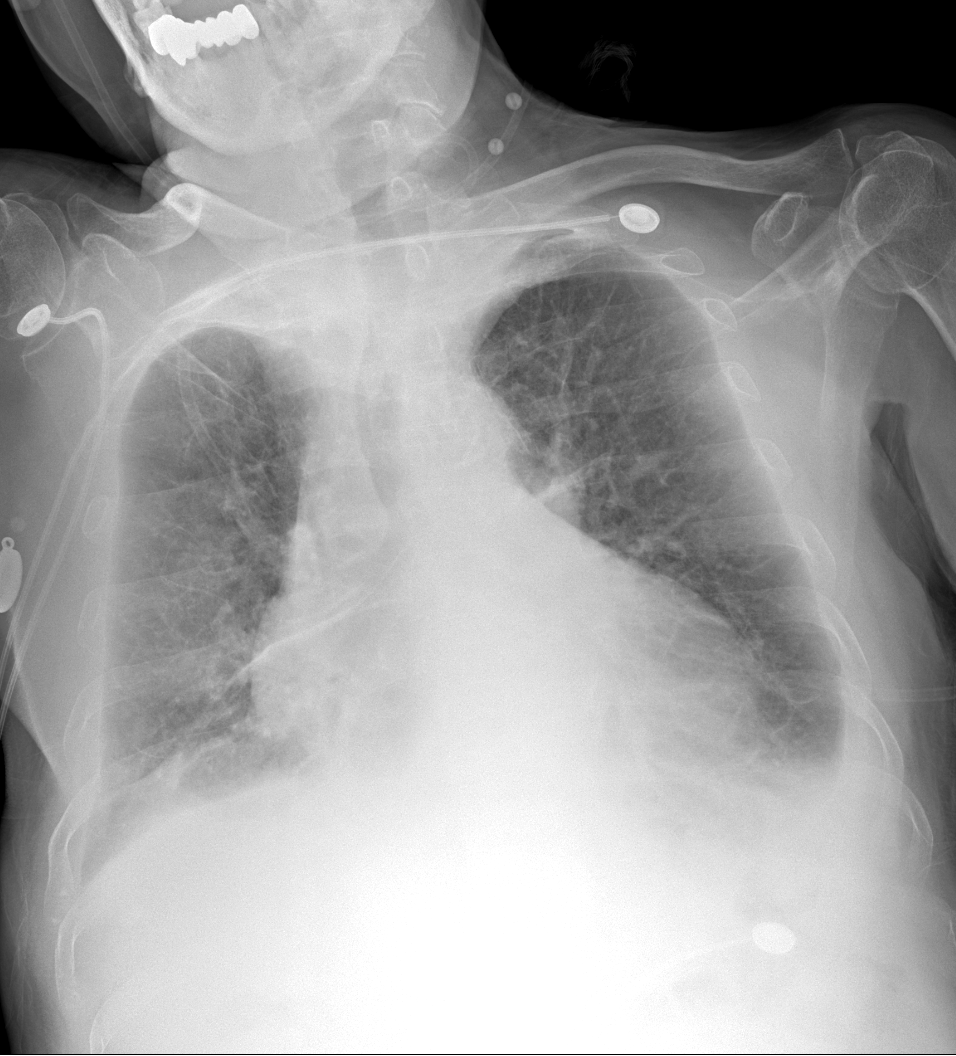

以上为同一位患者x光片。左图为床边拍片,右图为放射科固定机房设备拍摄的胸片,两图的清晰度及对病变的显示有区别。